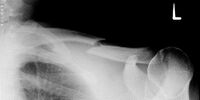

Mit Hilfe einer Röntgenaufnahme wird der Schweregrad der Verletzung abgeklärt. Es erfolgt entweder eine Behandlung mit Gips oder eine operative Versorgung. In der Rehabilitation unterstützen Mobilisations-, Kräftigungs-, Koordinations- und Ausdauerübungen den Heilungsprozess wesentlich. Die volle sportliche Belastbarkeit ist, je nach Bruchart, erst nach vielen Wochen der völligen Bruchheilung gegeben.

Schlüsselbeinbruch

Ein Schlüsselbeinbruch ist häufig die Folge von einem Sturz oder Schlag gegen das Schlüsselbein oder die Schulter, zum Beispiel beim Reiten, Fußball oder Skifahren. Dabei kann die bandartige Verbindung vom Schlüsselbein zum Schultergelenk reißen oder das Schlüsselbein brechen. Oft entsteht als Folge eine starke Schwellung und häufig ist eine Stufenbildung in der Schulter sichtbar.